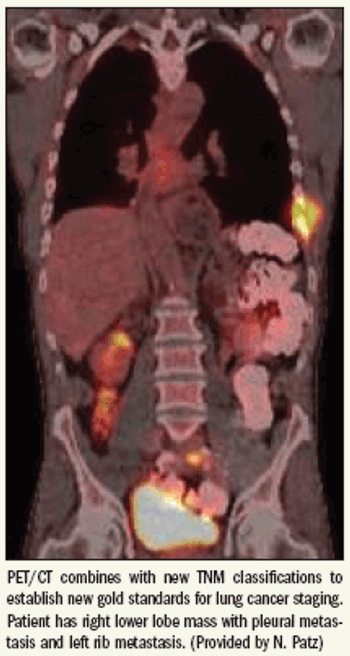

Radiologists may have to make only minor changes to their practices to adjust to the new international standards for lung cancer staging, but a lecture covering their implications was still controversial enough to send sparks flying.